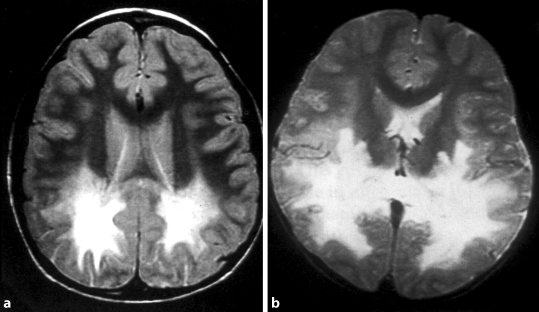

Abb. 4a,b

X-Adrenoleukodystrophie (X-ALD). Neurodegeneration bei Jungen im Schulalter mit X‑chromosomaler Adrenoleukodystrophie (ausgeprägte Leukodystrophie besonders um die Hinterhörner herum, kann aber auch frontal betont sein). Routinelabor ohne Auffälligkeiten; Suchtest: Bestimmung der überlangkettigen Fettsäuren im Plasma, die bei X‑ALD deutlich erhöht sind. Fallweise – nur im präsymptomatischen (?!) Stadium – Option zur Knochenmarktransplantation (© D. Karall)